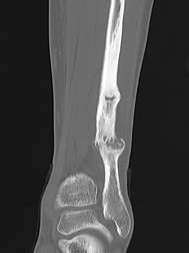

Xray

Cortical thickening

Look for "dreaded black line" - sign of fracture

Periosteal thickening with possible "dreaded black line"

Anterior cortical thickening with dreaded black line

CT